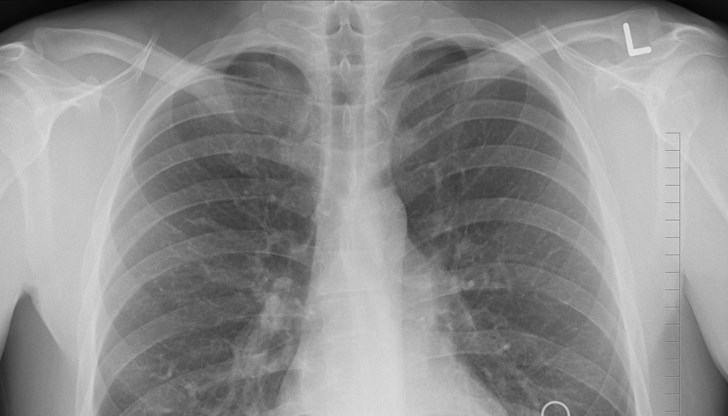

Археологическите находки доказват, че туберкулозата заразява хора още от 4000 г. пр.н.е. Mycobacterium tuberculosis - причинителят на болестта, идентифициран от Роберт Кох през 1882 г., притежава уникалната способност да остава в спящо състояние десетилетия наред. Когато се активира, атакува белите дробове, а понякога и други органи.

Българското Министерство на здравеопазването посочва основните симптоми, при които незабавно трябва да се консултираме с лекар: тежка кашлица с храчки, често със съдържание на кръв, и поддържане на висока температура. Придружаващи симптоми са болки в гърдите, отпадналост, липса на апетит и рязка загуба на тегло.